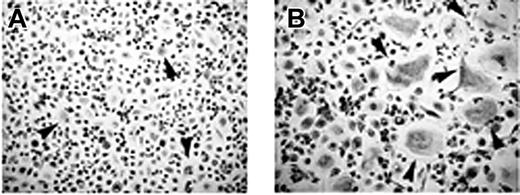

T cells mediate osteoclastogenesis in human MM PBMCs. Osteoclastogenesis occurred in T-cell–depleted MM PBMCs cultured in the absence (A) or in the presence (B) of M-CSF and RANKL. Small-sized OCs developed in the absence of M-CSF and RANKL (A), whereas exogenous cytokines triggered the formation of large-sized OCs (B). Multinucleated and TRAP+ cells were identified as OCs. The arrows point to the OCs (magnification × 200).

T-cell–mediated osteoclastogenesis and OC survival in patients with MM

The unstimulated cultures of T-cell–depleted PBMCs from patients with MM with osteolysis resulted in the development of few small-sized OCs (OC average number/well = 10 ± 2) (Figure 2A). By contrast, the addition of M-CSF and RANKL to these cultures induced the formation of numerous large TRAP+ OCs (OC average number/well = 68 ± 5) (Figure 2B), like those observed in the presence of T cells (Figure 1Aii). In the T-cell–depleted and stromal cell-free BM cultures, OCs did not form (data not shown).